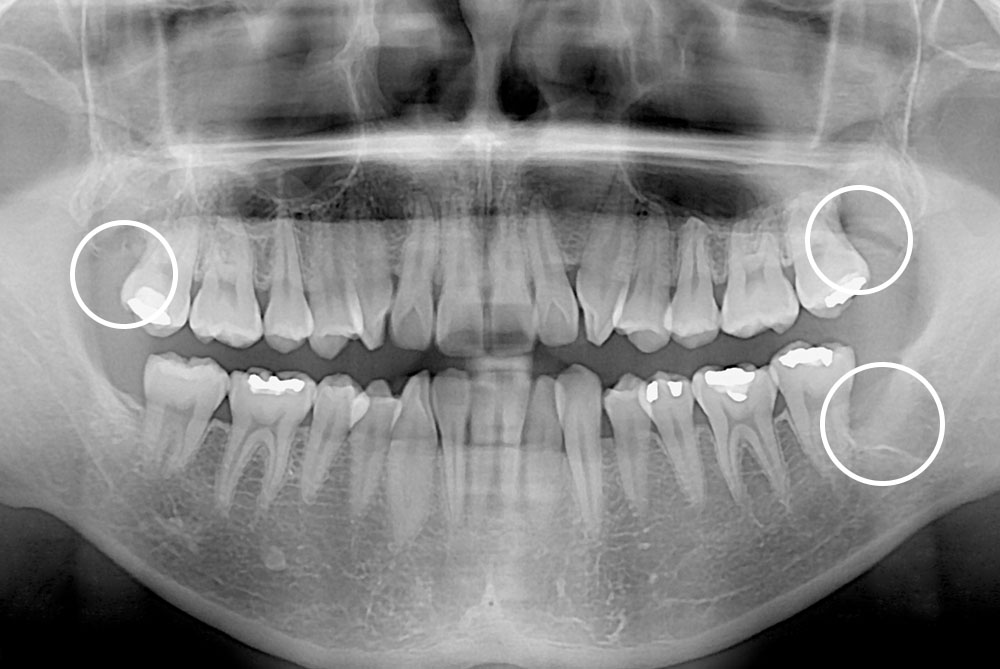

[사랑니] 매복 사랑니 발치

치료후 : 2018-10-25

세종치과는 구강악안면외과학 박사이신 원장님이 발치하는 치과입니다.